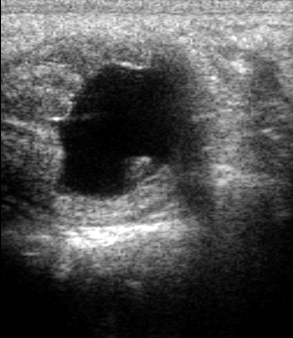

brak rui lub nieregularne cykle (ciąża i cykle płciowe nie wykluczają występowania GCT)

zwykle jeden jajnik znacznie powiększony, drugi nieaktywny (mieć na uwadze, że guzy mogą być obustronne)

> 30 pg/ml – podejrzenie ziarniszczaka lub przetrwałego pęcherzyka nieowulacyjnego

Ograniczenia: wynik badania należy rozpatrywać łącznie z obrazowaniem ultrasonograficznym.